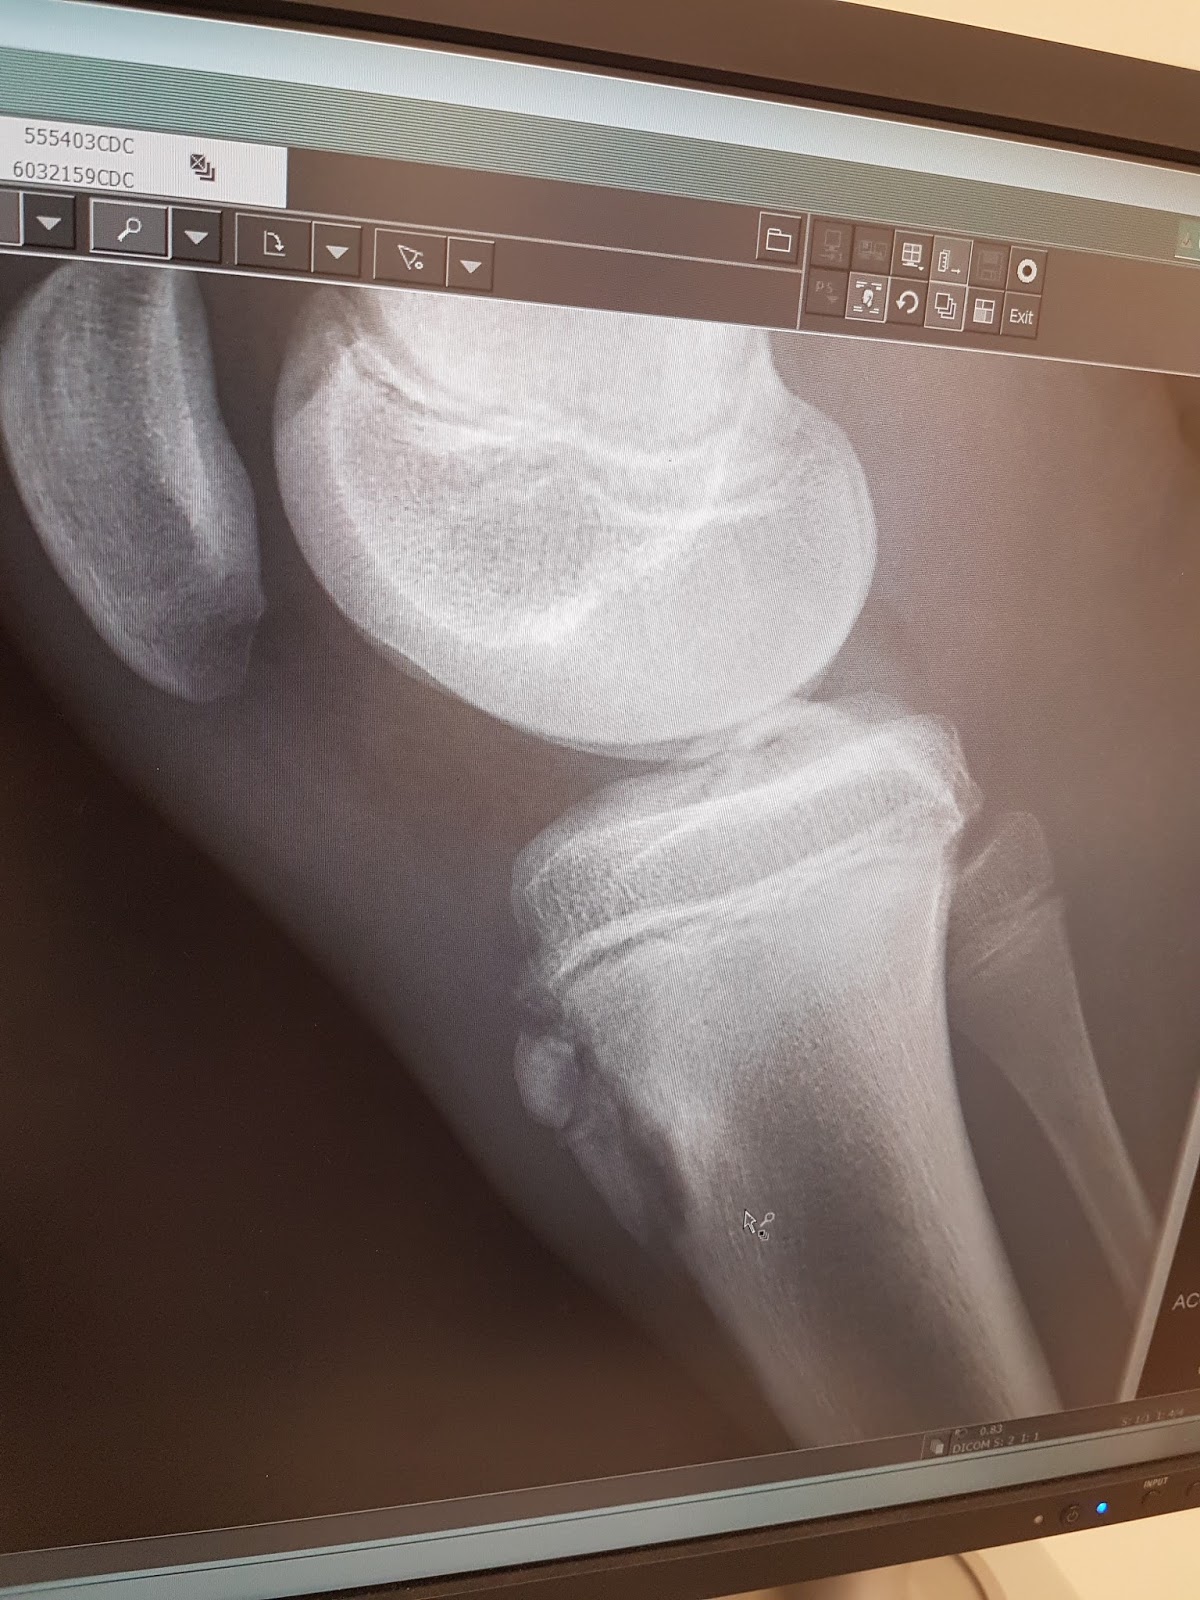

In June, Elijah was slowly starting back on events and continuing vault and floor (still no hands for the most part) when on June 22nd he 'tweaked' his right knee. He had not had any knee pain for some weeks and was actually being super careful after the hip strain in March. He said a simple front layout punch front layout double twist on rod floor to a soft mat caused some pain below the knee cap. He stopped tumbling and went on to other events. When I picked him up (it was a Thursday), he said, ' maybe no hike in Canmore this Saturday, I tweaked my knee'. To be safe, I booked a physio appointment the next day and Dr. Auld Monday. Physio thought it was just a strain, but Dr. Auld agreed we should get an x ray and ultrasound to be safe. Tuesday the x ray revealed a fracture of the tibia tuberosity at the growth plate. He could still jog on it! I asked for Dr. Phillips to review the x ray. She called Elijah in on Friday to say that there was no ligament or tendon damage, but she recommended open fixation (with screws) to re attach the pieces of bone and would do that July 5th during her on call day.

July 5th Elijah showed up at the Alberta Children's Hospital and fasted until an operating room became available at 5pm. It was a short successful surgery and an hour after, he was hungry and ready to move. We went home that night, Elijah equipped with his brace set to 180 degrees. It would be moved 30 degrees every week and a half after the 2 week check to ensure he regained as much motion and quad strength as possible.